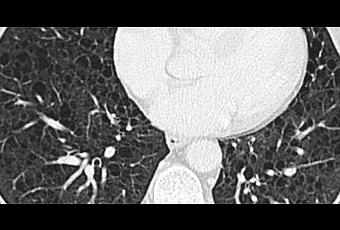

En la TAC se observan imágenes de quistes de paredes delgadas con infiltrados reticulonodulares.